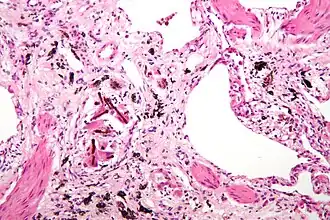

Micrografia de de asbestose (com corpos ferruginosos), um tipo de pneumoconiose. H&E stain.

• Asbestose - poeira de asbesto